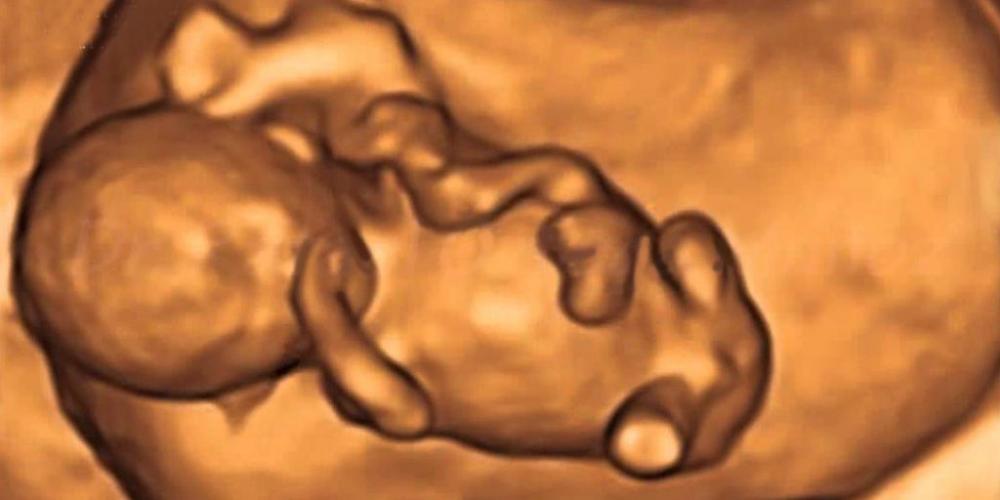

En los primeros 11 meses de este año, el Estado mató a 32.758 argentinos indefensos, inocentes, débiles, necesitados de protección, sin salida, acorralados, en condiciones de crecer y desarrollarse, de recibir y dar afecto, capaces de estudiar, de trabajar, de aportar soluciones al país.

32.758 argentinos que fueron deliberadamente asesinados por el sistema de salud público, invocando una ley injusta, aprobada con engaños, con corrupción, en el Congreso Nacional.

La directora nacional de Salud Sexual y Reproductiva, Valeria Isla dio a conocer la cifra de una masacre de seres humanos cuyos cuerpos fueron desechados, tirados a la basura, desde Diciembre de 2020. Pero si esa cantidad estremece, mucho más lo hace considerar que no se incluye a los niños asesinados en el vientre de sus madres en el sector privado, en servicios cubiertos por obras sociales y prepagas y aquellos que fueron sacrificados sin pasar por una institución de salud.